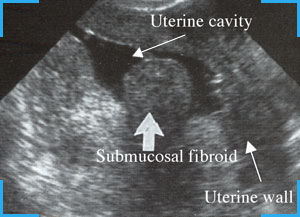

What is the best way to diagnose them? Ultrasound.